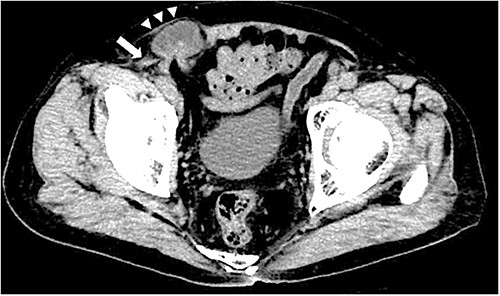

A 79-year-old male patient with a medical history of right inguinal hernia presented to the emergency department with right inguinal swelling and pain. We found the inguinal swelling, which extended toward the head, to be atypical. In addition, contrast-enhanced computed tomography (CT) scan revealed that a portion of the small intestine was incarcerated between the internal and external oblique muscles, and the hernia contents had prolapsed cranially from the hernial orifice. Furthermore, the sagittal view revealed that the contents of the hernia had prolapsed ventrally and not along the spermatic cord (Figs 1 and 2). Therefore, we diagnosed it as a right interparietal inguinal hernia, and laparoscopic hernia repair was planned. Owing to the fact that the manipulative reduction was difficult, we planned to release the incarceration first.

Contrast-enhanced CT scan; an incarcerated bowel was observed in the right inguinal region; the small bowel was incarcerated between internal and external oblique muscles; the white arrow indicates the internal oblique muscle, and the white triangles indicate the external oblique muscle.

Sagittal section of contrast-enhanced CT; the black triangles indicate the incarcerated small bowel.